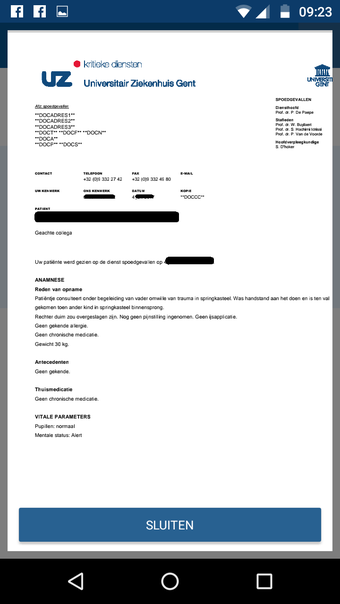

CoZo est une application de santé électronique qui permet aux patients et aux médecins de communiquer entre eux et de partager des informations médicales. Elle a été développée pour répondre aux problèmes du système de santé actuel, caractérisé par un manque de communication entre les patients, les médecins et les autres professionnels de la santé.

CoZo permet aux patients de prendre une part active dans leur propre santé et d'être traités comme des participants actifs dans le processus de soins. Les patients peuvent utiliser l'application pour enregistrer leurs données de santé, qu'ils peuvent ensuite partager avec leurs médecins. Les médecins peuvent utiliser l'application pour enregistrer l'historique médical de leurs patients, poser un diagnostic et suggérer un plan de traitement.